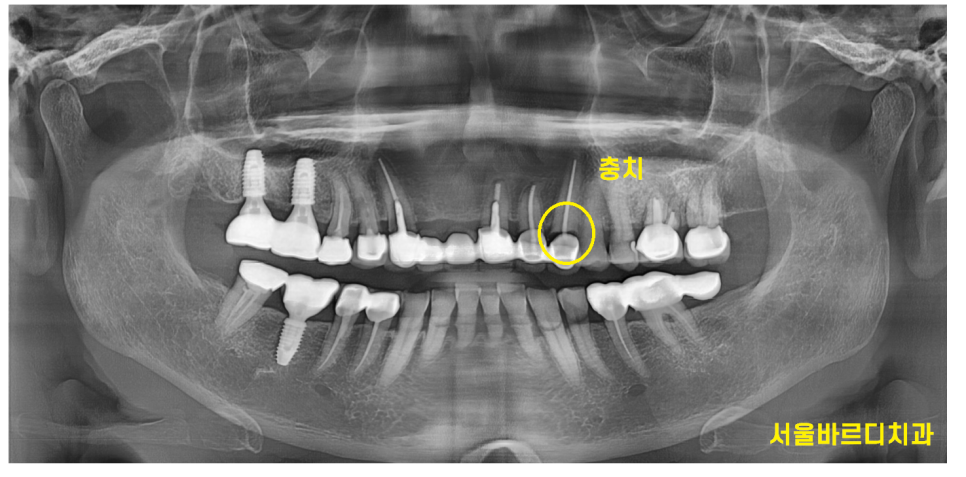

240307

240315

어쨌든 오늘 환자분도 충치가 원인이 되어

앞니 브릿지 파절을 유발했습니다.

신경치료가 안되어 있는 치아라면

보철부터 벗겨서 상태를 평가하는 것이 우선이지만

치아가 별로 안남을 때 치료하는 기둥이 박힌 치아가 2개

뿌리쪽 충치가 심한 치아 1개

치아가 거의 남아있지 않게 생겼습니다.

일반적으로 새로 치료를 할 때는 적어도 10년은 쓰셔야하는데

치아 상태들이 별로라

씹는 힘을 버텨낼 것 같지 않아보였습니다.

앞니 브릿지가 6개나 되는

길게 묶인 형태라서요~